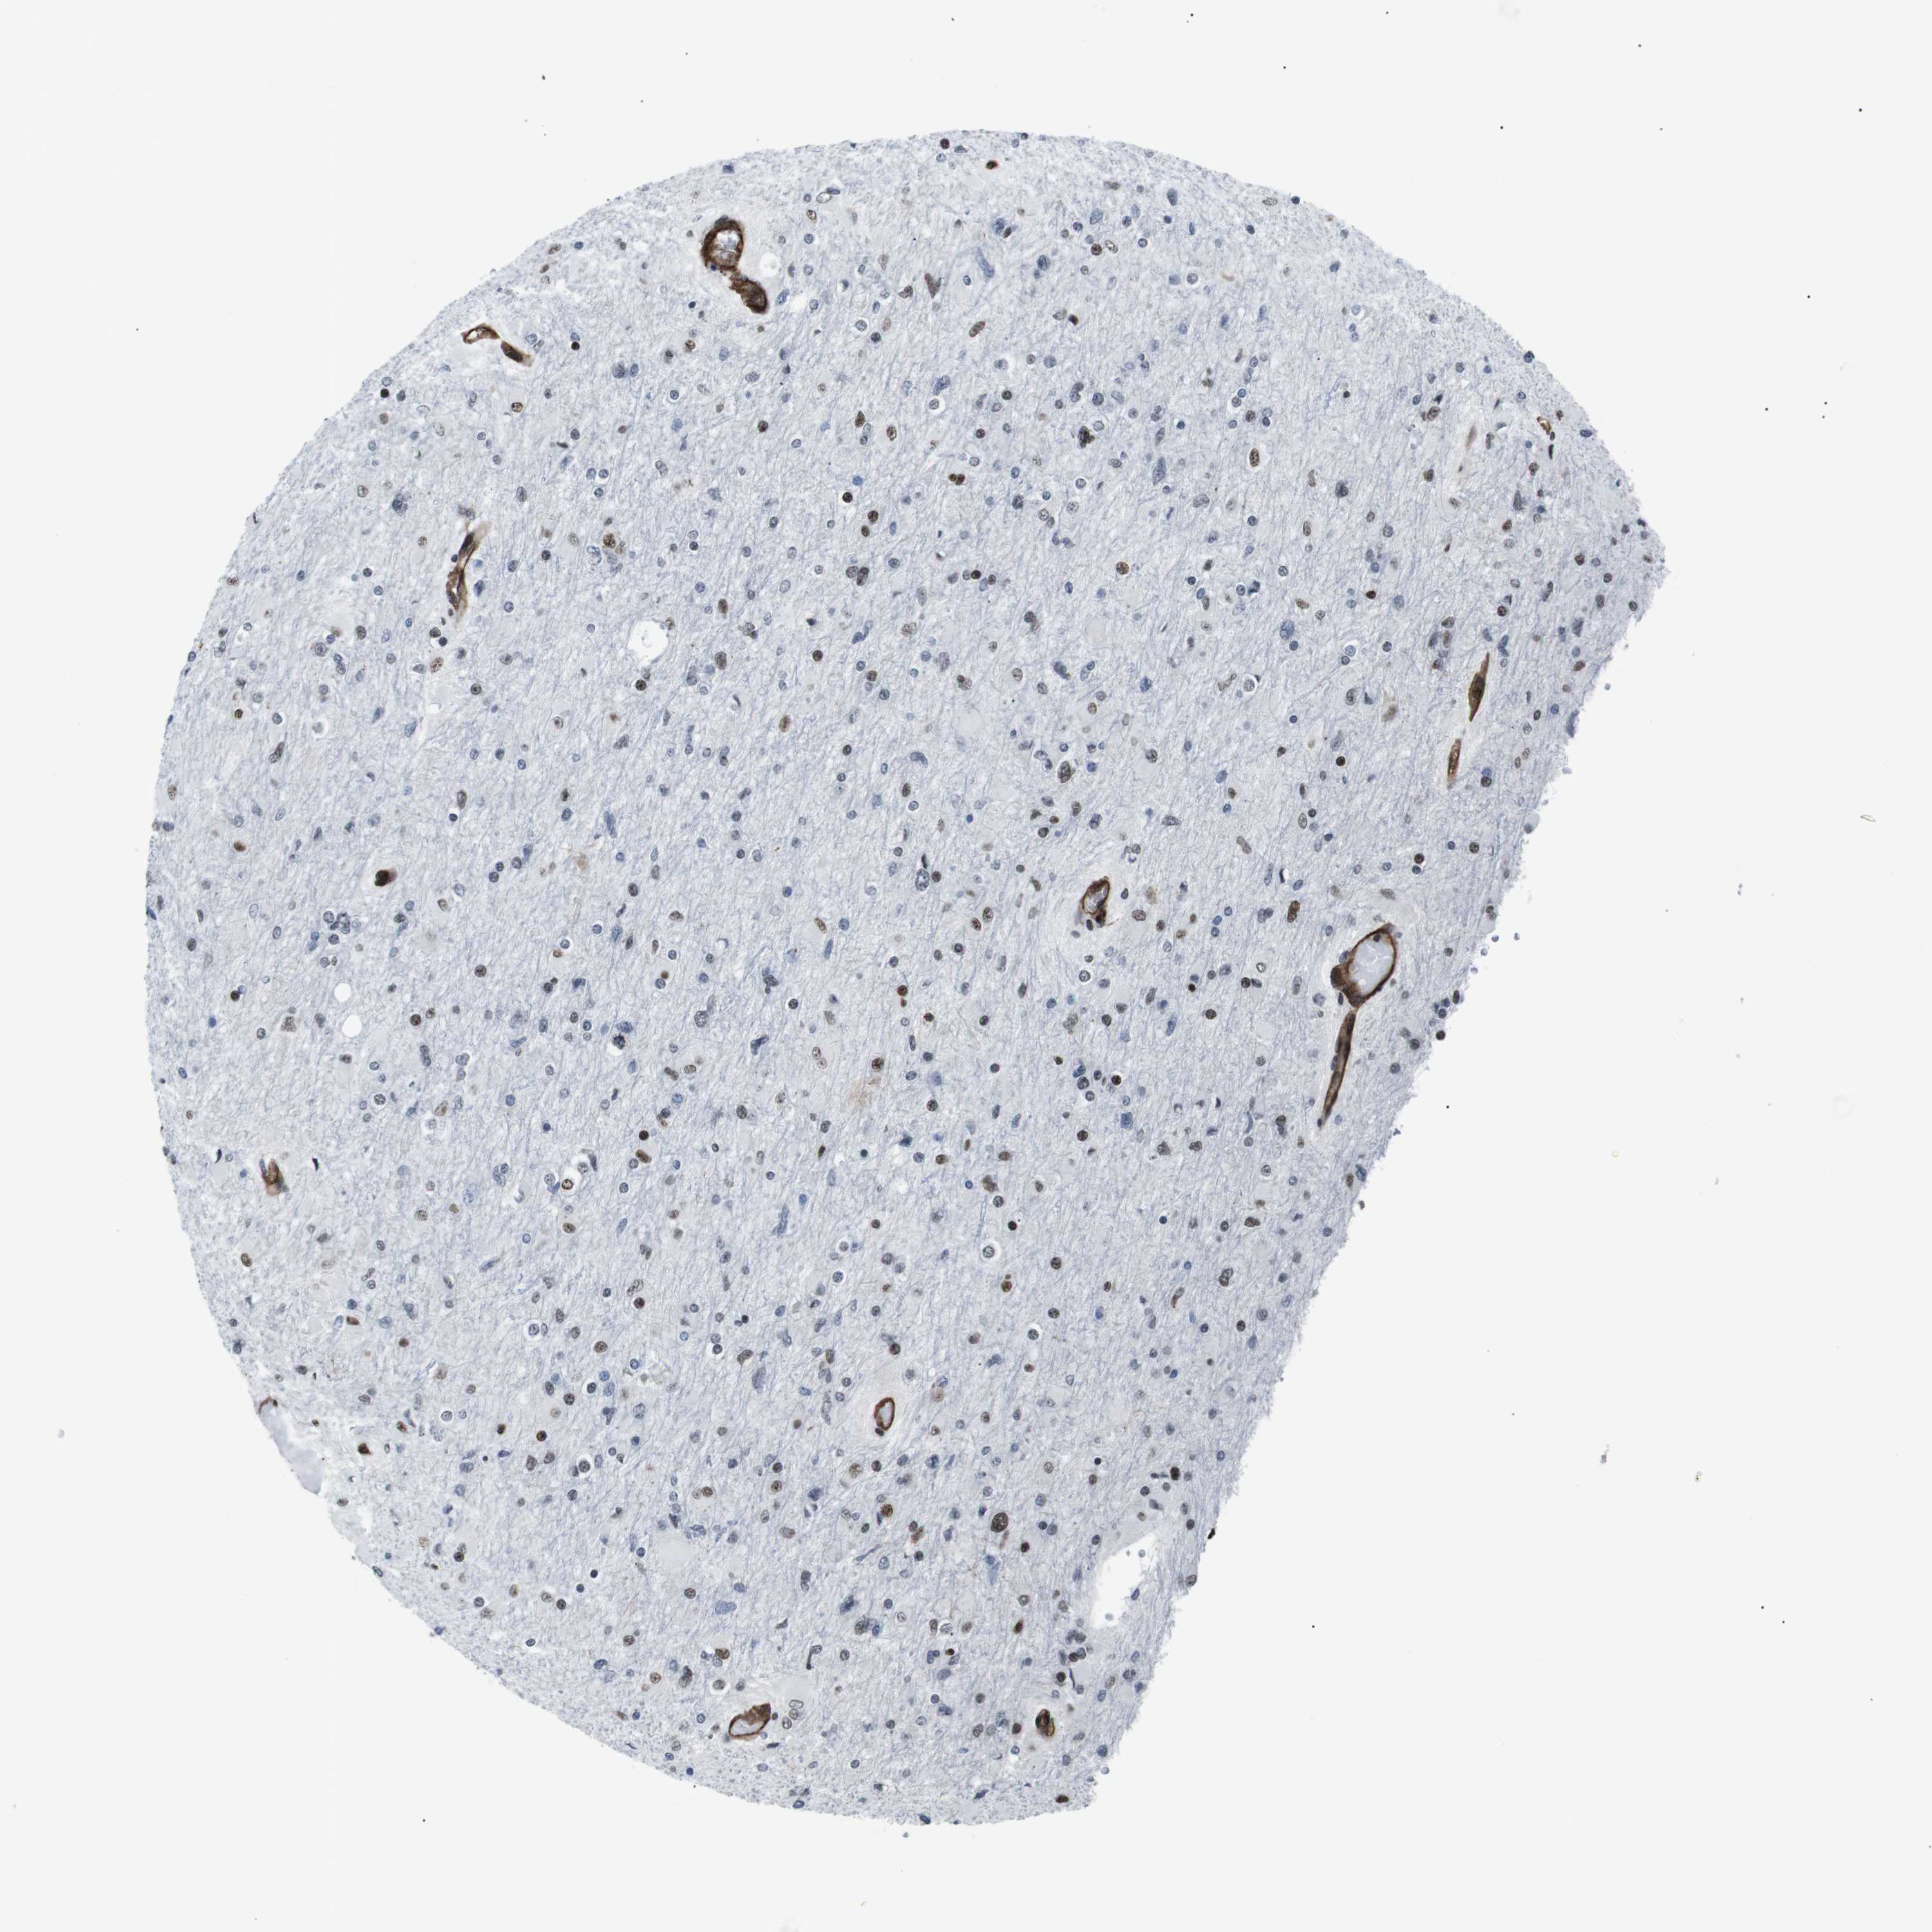

GLIOMA - Protein expressioni

A mouse-over function shows sample information and annotation data. Click on an image to view it in a full screen mode. Samples can be filtered based on level of antibody staining by selecting one or several of the following categories: high, medium, low and not detected. The assay and annotation is described here.

Note that samples used for immunohistochemistry by the Human Protein Atlas do not correspond to samples in the TCGA dataset.

Antibody stainingi

Antibody staining in the annotated cell types in the current human tissue is reported as not detected, low, medium, or high, based on conventional immunohistochemistry profiling in selected tissues. This score is based on the combination of the staining intensity and fraction of stained cells.

Each image is clickable and will lead to virtual microscopy that enables deeper exploration of all samples and also displays staining intensity scores, fraction scores and subcellular localization as well as patient and tissue information for each sample.

Antibody HPA041057

Antibody HPA058707

Antibody CAB011532

Staining

High

Medium

Low

Not detected

Intensity

Strong

Moderate

Weak

Negative

Quantity

>75%

75%-25%

<25%

None

Location

Nuclear

Cytoplasmic/membranous

Cytoplasmic/membranous,nuclear

Glioma, malignant, Low grade

Glioma, malignant, High grade